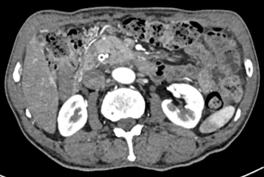

诊疗过程:患者高龄,一般情况差,手术风险高,患者及家属选择ERCP胆道支架植入及光动力治疗(不开刀、经自然腔道的微创手术,患者痛苦小)。ERCP术中因胆总管下段闭塞导丝不能进入胆总管,但是胰管插管成功,予以放置胰管支架(可改善胰管引流不畅,减轻胰管高压,改善消化功能);二期予以经皮经肝胆管穿刺(PTC)成功放置胆道支架(同样为微创,只需皮肤切开3mm的小口);待患者黄疸消退、全身情况改善后予以内镜下胆道肿瘤光动力消融术。术后多次复查腹部CT均提示胆总管下段肿瘤呈坏死的低密度灶,无复发征象。

术后6月复查CT显示胆管下段病灶仍无强化,提示病灶无进展